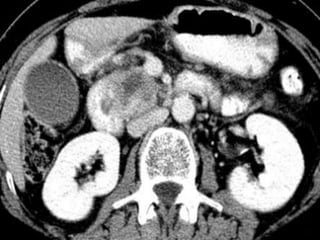

CT

 “Pancreatic protocol CT” is the gold

standard of investigation to stage the

disease and assess the operability

 Triple phase CT

 Closer cuts

 Water used as an intraluminal contrast

 Helical or multislice

 Focal or diffuse mass lesion which is hypo

dense (low attenuation) and hypo vascular

(poor contrast enhancement)

 Dilated MPD and CBD